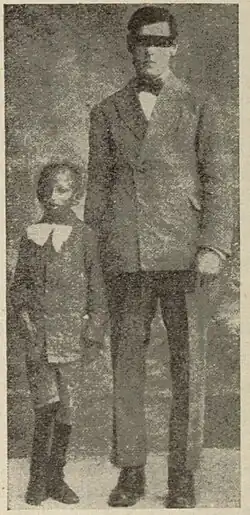

| A young girl with progeria (left). A healthy cell nucleus (right, top) and a progeric cell nucleus (right, bottom). | |